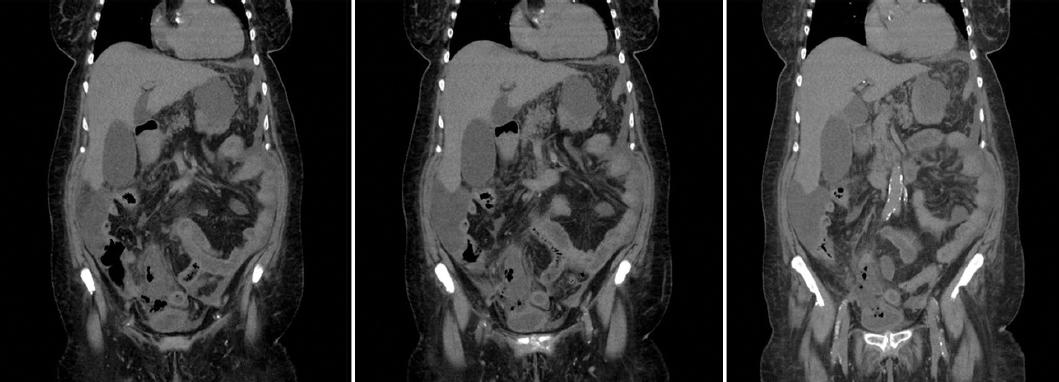

Los estudios de laboratorio mostraron leucocitosis de 45,000 con neutrofilia, tiempos de coagulación prolongados, lesion renal aguda y acidosis metabólica. La TC reportó líquido libre de predominio en la corredera parietocólica derecha, colección intraabdominal paracecal en proximidad con la vejiga, gas en la cavidad, ligero engrosamiento de la pared vesical y una zona de interfaz entre el ciego y la vejiga (Fig. 1). Se diagnosticó como probable apendicitis aguda complicada con perforación vesical secundaria.